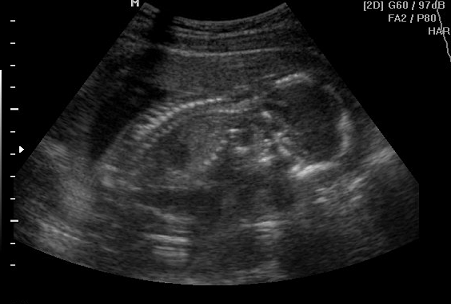

Преимущества УЗИ: Современные методы диагностики